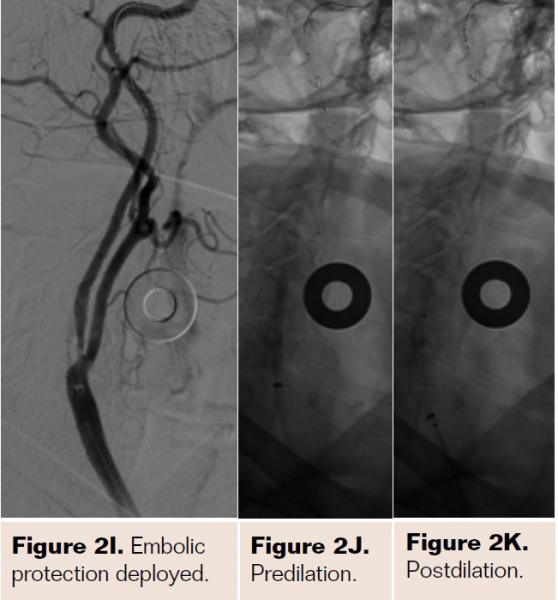

Pretreatment with dual-antiplatelet therapy (DAPT) was started 4 days prior to the procedure with aspirin and clopidogrel, with 600 mg loading dose of clopidogrel and 80 mg dose of atorvastatin the morning of the procedure. The right radial artery was accessed with a 6 Fr Terumo radial sheath, but intraarterial nitroglycerin was not administered due to a prior history of profound hypotension with sublingual nitroglycerin. Verapamil was withheld due to a systolic blood pressure of 130 mm Hg. Both right and left anterior oblique arch aortograms with a 5 Fr straight pigtail catheter demonstrated patency of the proximal great vessels, a type I aortic arch, and a calcified proximal right internal carotid artery (ICA) high-grade stenosis with patent right external carotid artery (ECA). The right common carotid artery (CCA) was selected with 5 Fr internal mammary (IM) diagnostic catheter that confirmed an 85% proximal right ICA stenosis. A soft-angled .035˝ Glidewire (Terumo) was advanced into the right ECA, exchanged out for an Amplatz .035˝ super-stiff wire (Boston Scientific), followed by removal of the diagnostic catheter, and radial sheath. A 6 Fr Shuttle sheath (Cook Medical) was delivered into the distal right CCA. After intracranial angiography, a NAV-6 Emboshield (Abbott Vascular) was deployed in the distal extracranial ICA, followed by predilation with a 4 x 30 mm Trek (Abbott Vascular), and deployment of a 7 x 30 mm Precise self-expanding stent (Cordis). Postdilation was performed with a 5 x 20 mm Maverick NC balloon (Boston Scientific), and then with a 6 x 20 mm Aviator balloon (Cordis) in order to then deliver the retrieval catheter. After repeat angiography confirmed an excellent result, the Shuttle was removed, and hemostasis achieved with TR band (Terumo) (Figures 2A-2R).